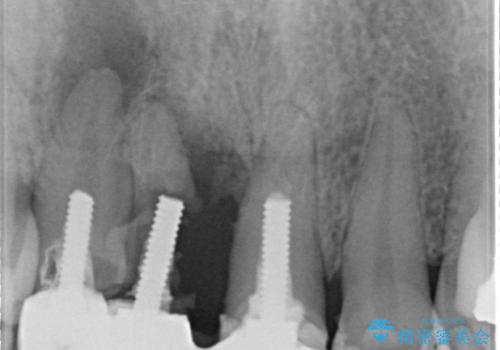

レントゲンを撮影すると保存が難しい歯がありました。

またがたつきの度合いから歯を1本抜歯して矯正治療を行いセラミックブリッジを装着することで、審美的・機能的改善を行う計画としました。

①保存不可の歯の抜歯・根管治療